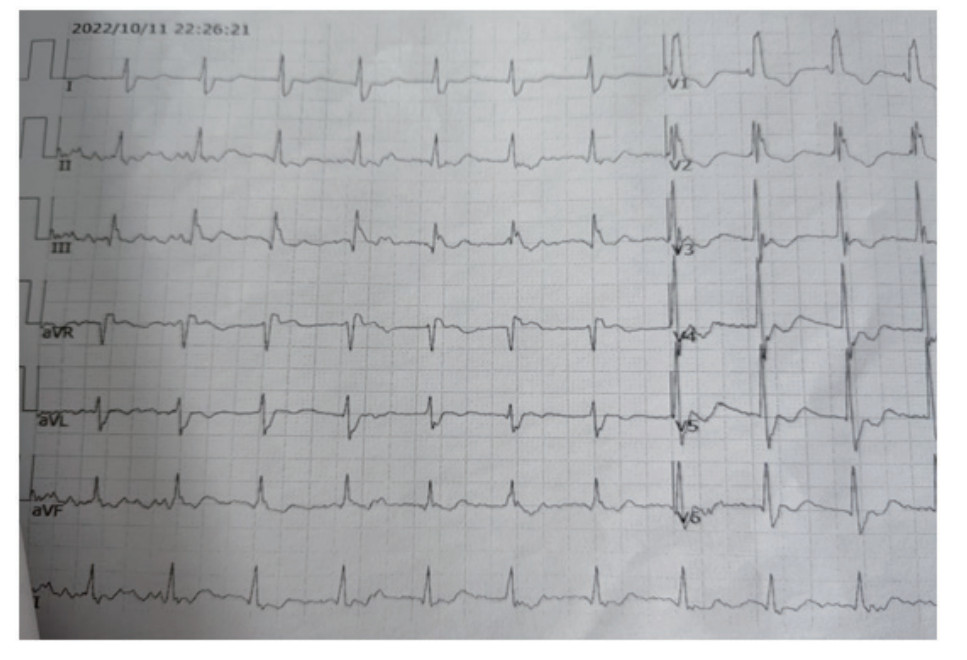

患者,男性,59岁,2022年10月11日21:42:26,九江市医疗急救中心调度员接到报警电话,家住某小区患者猝然倒地,意识不清, 呼之不应。21:43:02调度员派出救护车,同时启用ADLS,并应用ADLS中的CPR预案判断现场环境安全和确定患者为心脏骤停后,立即安抚报警人情绪,让其遵从120调度员的在线指导,将患者放于地面上,跪于患者右侧,双手交叠置于两乳头连线的正中间,始终保持手肘伸直,用手掌根部快速用力向下按压5~6 cm, 并通过ADLS中的计数工具指导报警人按压的频率,指导界面见图 1。21:54:02(接警后11分36秒)救护车到达现场接替报警人,并开始实施高级生命支持,急救人员建立静脉通路,静脉推注肾上腺素并持续心肺复苏术。22:03:29院前首份心电图提示心室颤动(图 2),急救人员立即进行除颤200 J;22:07:04心电监护仍提示为室颤,急救人员进行第二次除颤200 J,22:26:21现场心电图转为窦性心律(图 3),急救人员现场复苏成功,恢复患者自主循环, 口唇由发绀转为红润,瞳孔由大变小(直径由6 mm缩小为3 mm),遂将患者以“心脏骤停复苏成功、心源性休克”立即送往院内进一步诊治。患者既往两次脑梗死病史、高血压病史,个人史、过敏史、家族史无特殊。

图 3 患者现场除颤后心电图示窦性心律